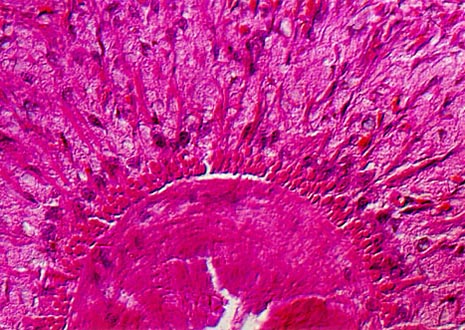

Planaria are primarily free-living flatworms that are members of the class Turbellaria. Observers can go "fishing" for the invertebrates, which frequent the sediments of ponds and lakes, by simply tossing a piece of liver attached to a string into the water.